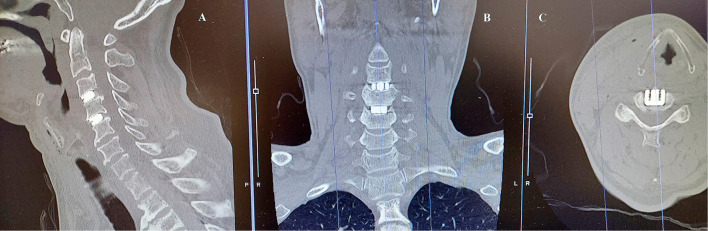

Gelatin-based hemostatic agents are widely used in neurosurgery. This is a case of postoperative aphagia strongly suspected to be caused by an allergic reaction to a gelatin-based hemostatic agent after anterior cervical decompression and fusion for central cervical cord injury. A 55-year-old man underwent cervical anterior decompression and fusion at the C3/4 and 4/5 levels for central cervical cord injury. Immediately after the surgery, he could not swallow saliva at all, but his voice was not hoarse. Postoperative cervical computed tomography and magnetic resonance imaging showed significant edema from the post-hypopharynx wall to the front of the vertebral body. The retropharyngeal space was remarkably enlarged to 15.8 mm with cervical spine X-rays. Without neurological symptom improvement, his condition was diagnosed as marked edema of the area where Surgiflo (porcine-derived gelatin-based hemostatic agent; Johnson & Johnson Wound Management, Somerville, NJ, USA) had been applied during the operation. It was strongly suspected to be caused by an allergic response to the porcine-derived gelatin. When methylprednisolone 1000 mg was administered for 3 days from the 5th postoperative day, swallowing became almost normal within a few hours after the initial administration, and his neurological symptoms improved. The patient left the hospital on the 12th day after the operation. Before using porcine-derived gelatin products during surgery, special consideration should be given to patients with an allergy history before surgery.

明胶类止血剂广泛应用于神经外科。这是一例术后失语症,强烈怀疑是由于前路颈椎减压融合治疗中心性颈髓损伤后对明胶止血剂的过敏反应引起的。55岁男性因中心性颈髓损伤行颈椎前路减压和C3/4和4/5节段融合术。手术后,他完全无法吞咽唾液,但声音并不沙哑。术后颈椎计算机断层扫描和磁共振成像显示从下咽后壁到椎体前部明显水肿。颈椎x线片显示咽后间隙明显增大至15.8 mm。神经系统症状没有改善,他的病情被诊断为Surgiflo(猪源明胶止血剂;强生伤口管理公司(美国新泽西州萨默维尔)在手术中应用。人们强烈怀疑这是由对猪源明胶的过敏反应引起的。术后第5天起给予甲强的松龙1000 mg,连续3天,术后数小时吞咽基本恢复正常,神经系统症状改善。患者于术后第12天出院。在手术中使用猪源明胶产品之前,应特别考虑术前有过敏史的患者。